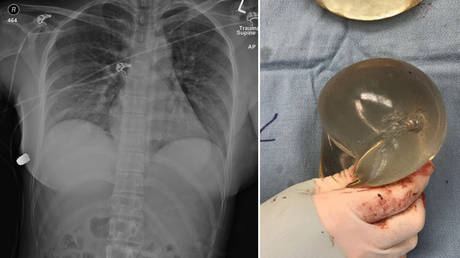

Doctors in Canada have reported a truly bizarre case, which they believe is the first of its kind, in which a woman’s breast implants saved her life by stopping a bullet headed straight for her heart. The surreal incident took place in Ontario, Canada and is the subject of an ongoing investigation in which neither the shooter, nor the firearm used were ever found.  The 30-year-old woman was reportedly on a night out when she suddenly felt a sharp pain and intense heat in her chest. She looked down in horror and discovered she was bleeding so she rushed to the emergency room of a local hospital.